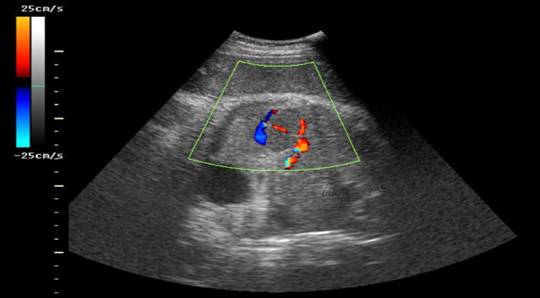

如果需要,临床医生也可浏览相应的彩超图像